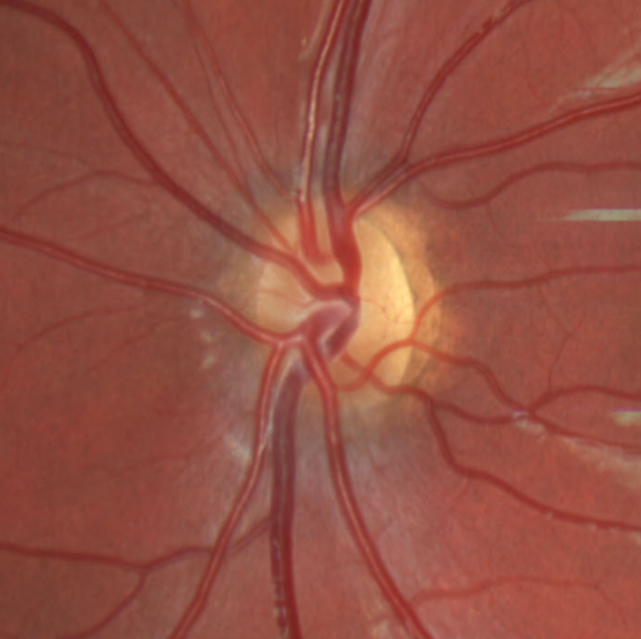

On ophthalmic examination there is typically evidence of optic atrophy with pale optic discs. There can also be excavation or hypoplasia of the optic discs.[2] Patients also commonly present with nystagmus, cortical visual impairment, and alacrima.[11]